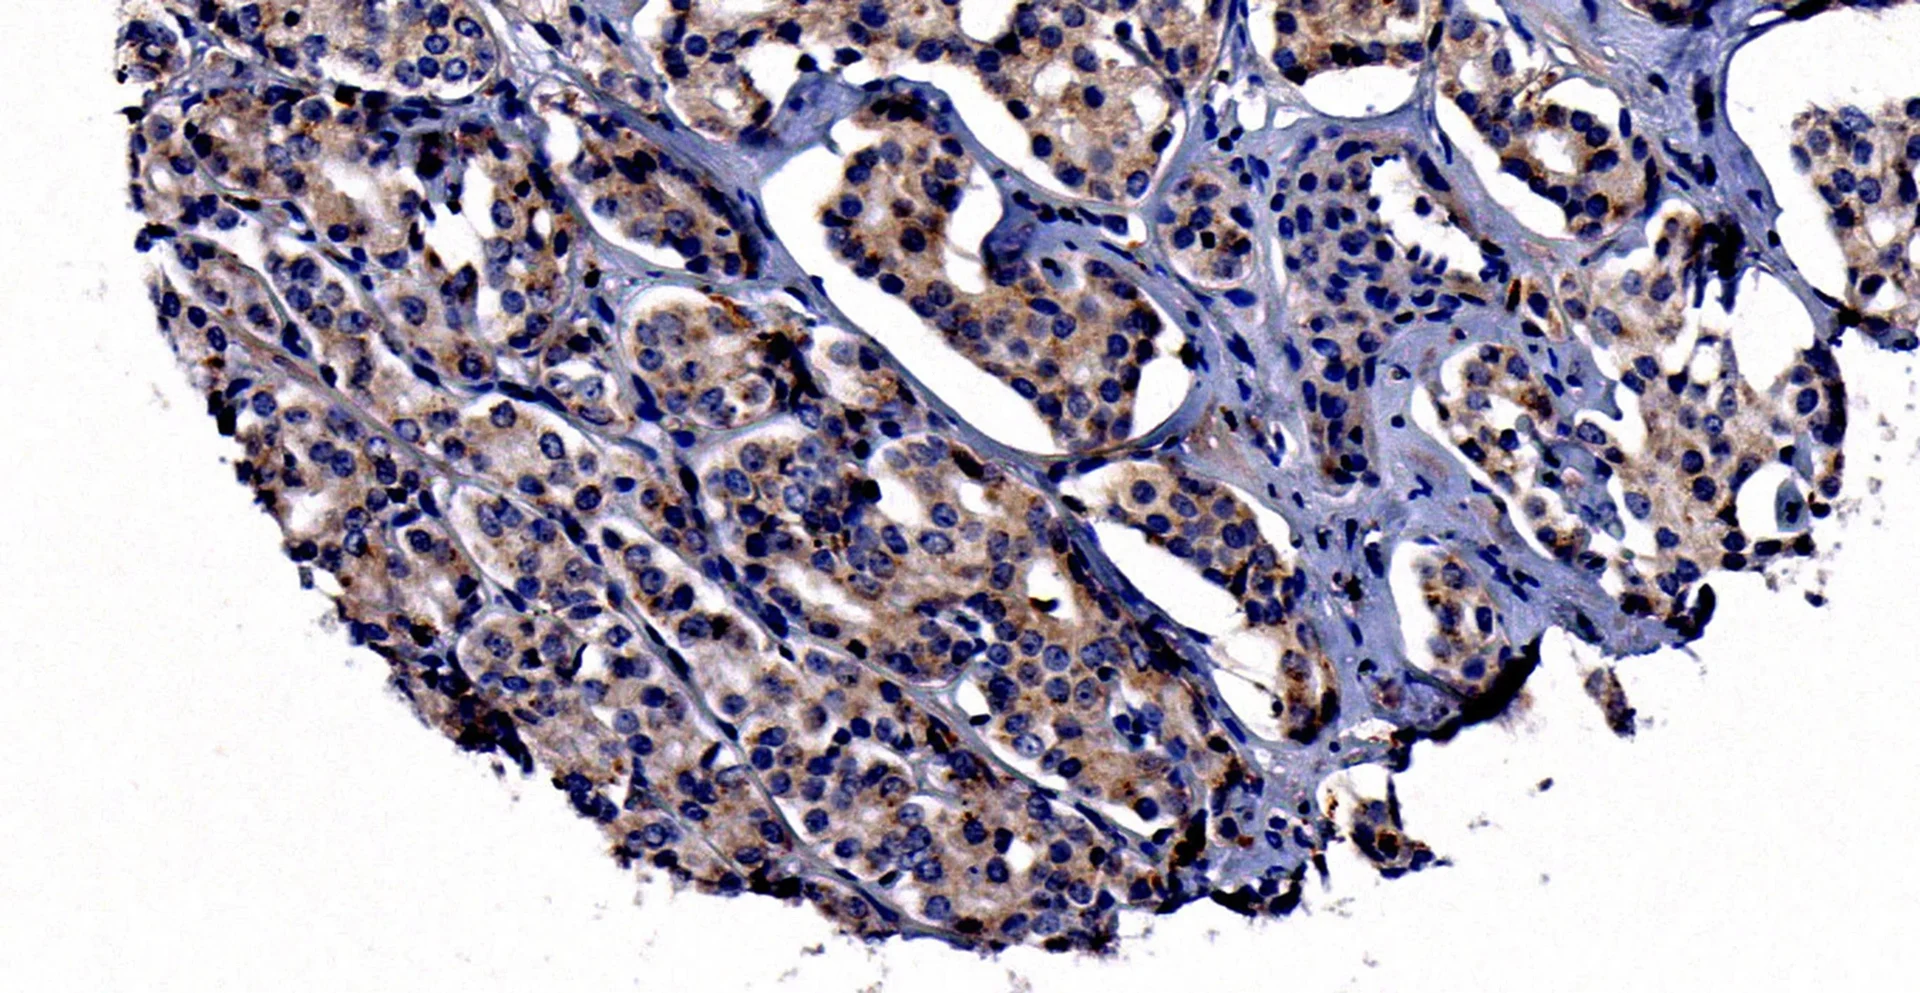

Metastasierte Prostatakarzinomzellen

Metastasierte Prostatakarzinomzellen - mit einer starken Expression des Neuropilin-2-Proteins (bräunliche Farbe). Das Gewebe wurde zunächst mit EDTA schonend entkalkt, um dann mit Hilfe von Neuropilin-2 spezifisch detektierenden Antikörpern gefärbt zu werden. © Muderslab